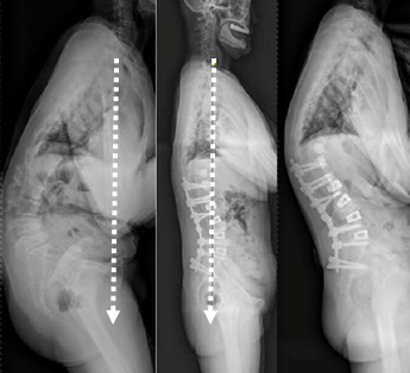

1) 矢状面失平衡(High SVA)过度矫正

术前-术后SVA矫正过大(大于5cm)的患者,PJK发生的风险增高

矫形术后矢状面失平衡可增加固定融合近端和远端交界区的应力,增加PJK风险

图16 矢状面失平衡过度矫正

2)腰椎前凸(LL)过度矫正

图17 据文献报道,腰椎前凸(LL)过度矫正和SVA基线位置不当,均为增加PJK发生的风险因素